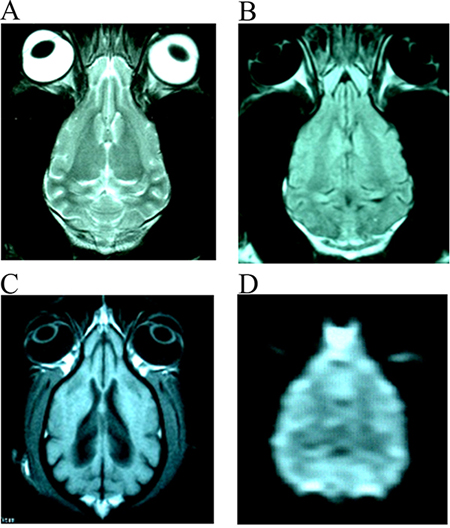

After stroke, the signal intensity of lesion in DWI images were increased gradually in those without treating canines at 0.5 h, 6 h and 24 h. In those treated canines, the signal intensity of DWI images at different time points also increased, but were not so evident like those untreated canines (Supplementary Figure 1). The images (DWI, T1WI, T2WI and FLAIR sequences) of infarction focus in group E at each time point were more serious than that of groups A-D at the range and signal intensity of the focus. There was no abnormal MRI scan in the F group at each time point (Figure 1).

Figure 1: The normal images of T2WI (A), FLAIR (B), T1WI (C) and DWI (D) from the same slice of canines’ brain.